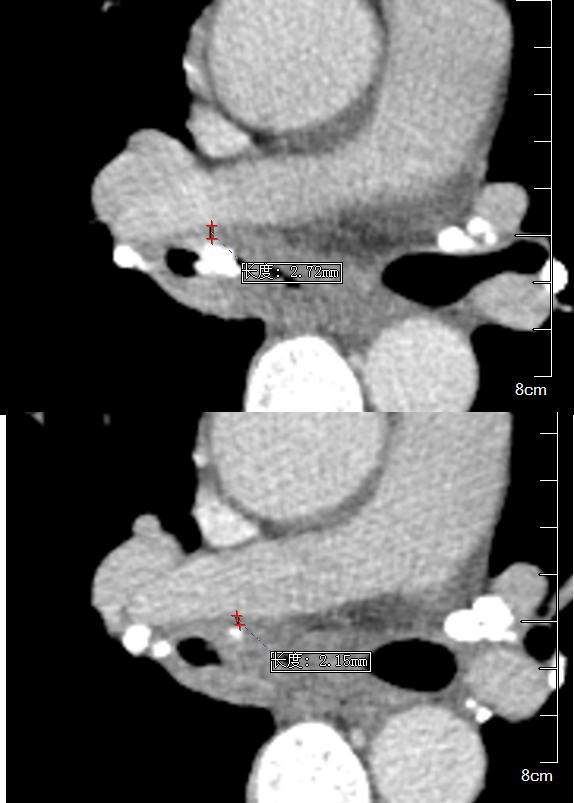

另外,这个患者的钙化灶非常危险,因为钙化灶的一端距离肺动脉才2毫米左右(图17),支气管镜下强行牵拉钙化病灶很可能会大出血危及生命。

图17 胸部CT